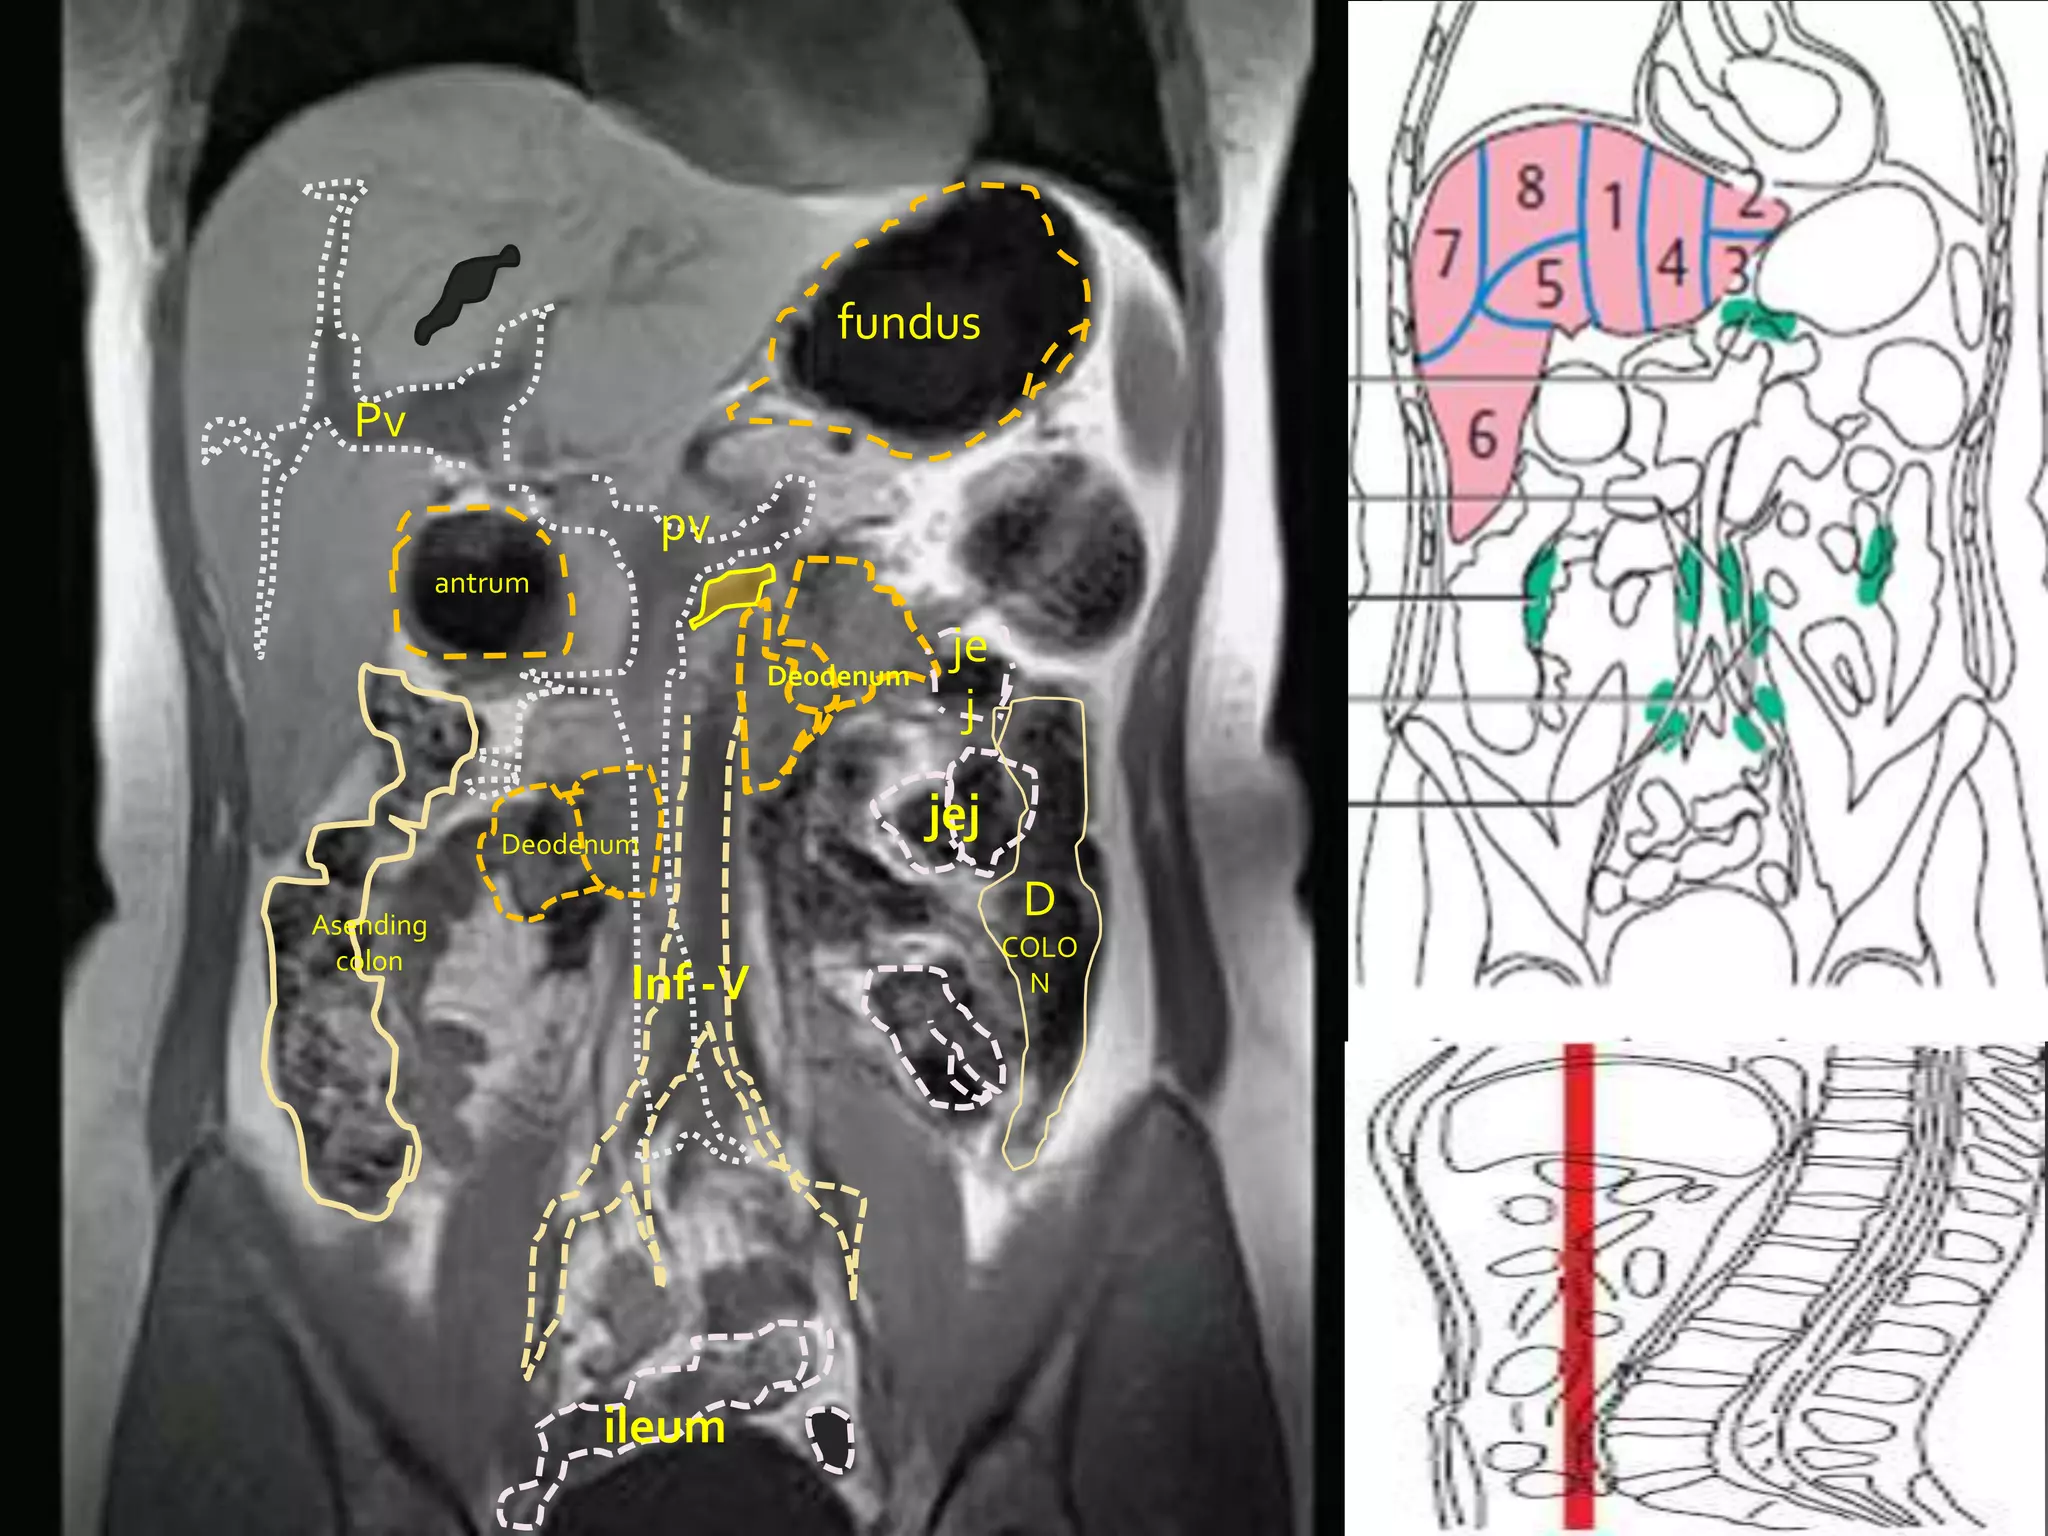

Pv

antrum

Deodenum

je

j

jej

Asending

D

colon                                          COLO

Inf -V                     N

ileum